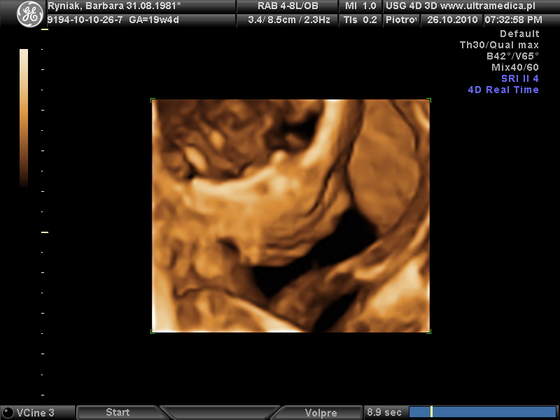

Głównie czytam, co piszecie, nigdy sama nie pisałam. To teraz pomyślałam, że dam znać że też mam termin w marcu a we wtorek byłam na usg 3D/4D. Szczerze mówiąc naprawdę marzyłam, żeby była dziewczynka i... na 90% będzie to dziewczynka. Moja fasolka przeciągle ziewała podczas badania, była chyba znudzona albo wyraźnie śpiąca (ok. 19:00) i mimo że się nie ruszała specjalnie i nie wierciła to lekarz miał trudności z ustaleniem płci. Fasolka jakby nóżki zaciskała. W końcu stwierdził zatrzymując głowicę na kroczu fasolki, patrzy patrzy i mówi, że na jego oko to są zaczątki warg sromowych i na 90% będzie to dziewczynka. I tak się zastanawiam czy istnieje możliwość że te wargi się przeistoczą jeszcze w peniska?

dzidzia waży 490g ,22 cm. Wszystkie wymiary są jak najbardziej w normie i tyle powinny mieć. Łożysko mam na tylnej ścianie, szyjka prawidłowa, serduszko dziecka również. Lekarz stwierdził ,że wygląda na inteligentnego bo najpierw pokazał nam tyłeczek i jajeczka, potem śmiał się , a później na 3D miał rączkę przy główce tak jakby myślał

....o tak: